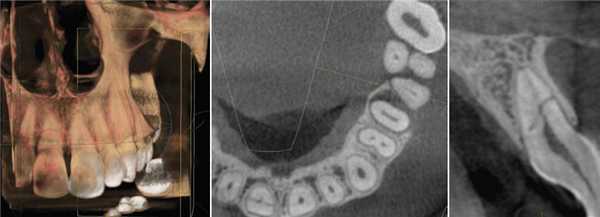

ОПМГ достоверно передавали взаимоотношение выведенного из КК пломбировочного материала с корнями зубов и анатомическими деталями зубочелюстных сегментов. В большинстве случаев отображение пломбировочного материала в проекции дна верхнечелюстных пазух или нижнечелюстного канала не позволяло определить, находится пломбировочный материал вне или внутри этих анатомических образований. В подобной ситуации данные КЛКТ приобретали решающее значение (рис. 7, а, б).

Рис. 7. Исследование области зуба 2.7 и дна верхнечелюстной пазухи слева. а — на фрагменте ОПМГ в проекции дна верхнечелюстной пазухи виден пломбировочный материал, выведенный из корня 2.7; создается ложное впечатление о проникновении пломбировочного материала в пазуху; б — на косом срезе КЛКТ пломбировочный материал, выведенный из небного корня зуба 2.7, располагается вне пазухи, у ее внутренней стенки.

КЛКТ предоставляла достоверные сведения о качестве обтурации КК всех групп зубов, наличии незапломбированных и неправильно запломбированных КК (рис. 8, а, б, в), перфорации корней зубов (см. рис. 6, б).

Рис. 8. КЛКТ. а — не запломбирован небный корень зуба 1.6; б — щечные корни зуба 1.7 обтурированы не на всем протяжении; в — неоднородное заполнение пломбировочным материалом КК зуба 2.6.